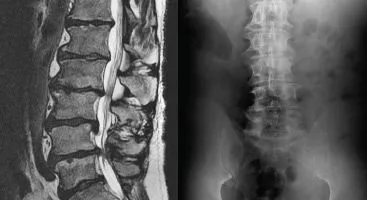

Multiple Severe Disc Herniations & Degeneration Lumbar Spine

Over the course of seven years, Bruce developed lower back pain that increasingly radiated down his left leg into his foot and eventually became disabling.